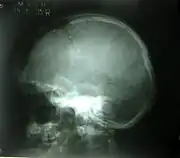

Different features of the dysostosis are significant. Radiological imaging helps confirm the diagnosis. During gestation (pregnancy), clavicular size can be calculated using available nomograms. Wormian bones can sometimes be observed in the skull.[20]

Lateral skull radiograph showing open skull sutures, large fontanelles, multiple wormian bones and underdeveloped paranasal sinuses.